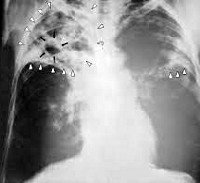

Основную диагностическую информацию о специфике заболевания дает рентгенография легких. На рентгенограммах обнаруживается затемнение пораженной доли или сегментов, патологически измененный участок легкого уменьшен в размерах. На фоне затемнения могут выделяться более светлые участки (бронхоэктазы, каверны). Плевра утолщена, тень средостения смещена в сторону поражения. Особенно четко описанные изменения видны на томограммах. Ранее для выявления изменений со стороны бронхов в зоне цирроза широко использовалась бронхография, однако в настоящее время ее успешно заменяет КТ легких.